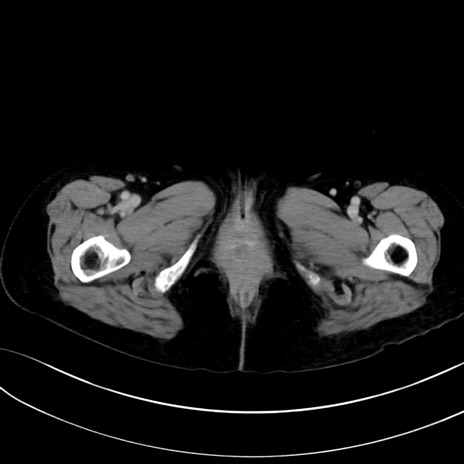

症例13 CT(横断像)1日半後